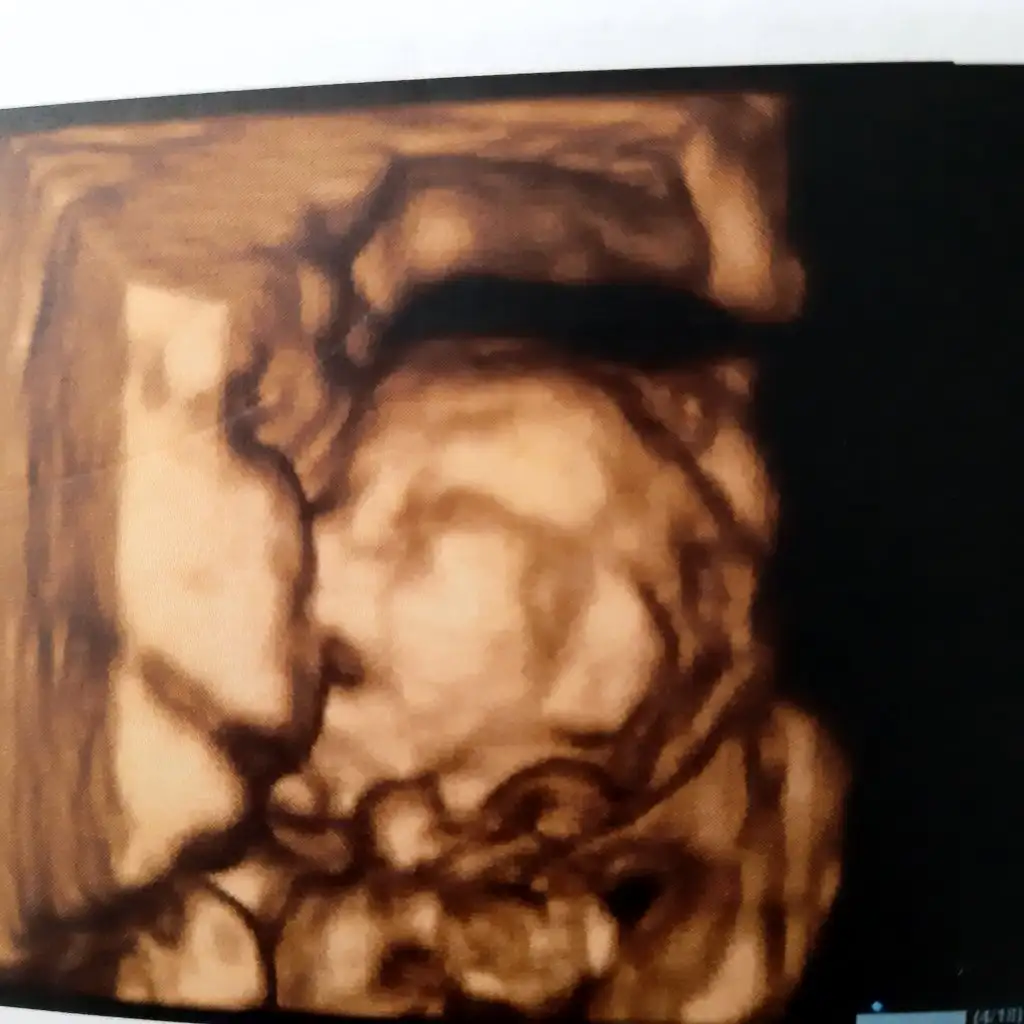

Minik burunlu

Köfte dudaklı bir kız

Yaaaa çok güzelUyuyordu .tofıta atmıştım ağzına ama.geç yattım gece

Yaa maşallah dudaklar hakkaten köfte:)))Uyuyordu .tofıta atmıştım ağzına ama.geç yattım gece

Sağ ol canim. Karından bakılıyorYaa maşallah dudaklar hakkaten köfte:)))